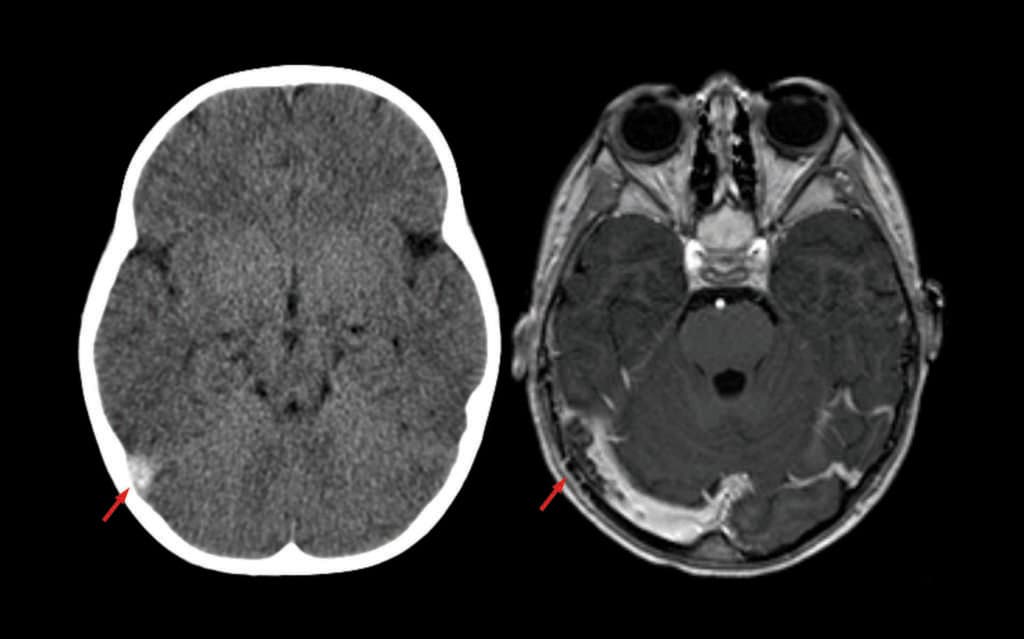

CT ohne und MRI mit Kontrastmittel zeigen beide den Befund einer SVT (Pfeil) beim selben Patienten.

Sobald der klinische Verdacht auf eine Sinusvenenthrombose gegeben ist, muss eine bildgebende Diagnostik erfolgen, betonte der Angiologe. CT und MRI – beide mit venöser Angiografie – sind als gleichwertig anzusehen. Bei kortikaler Venenthrombose ist das MRI aber deutlich überlegen. Auch bei jüngeren Patienten und in der Schwangerschaft ist das MRI wegen der geringeren Strahlenbelastung vorzuziehen. Ein D-Dimer-Test spielt bei SVT eine eher geringe Rolle – insbesondere die Entscheidung für oder gegen eine zerebrale Bildgebung sollte nicht davon abhängig gemacht werden.